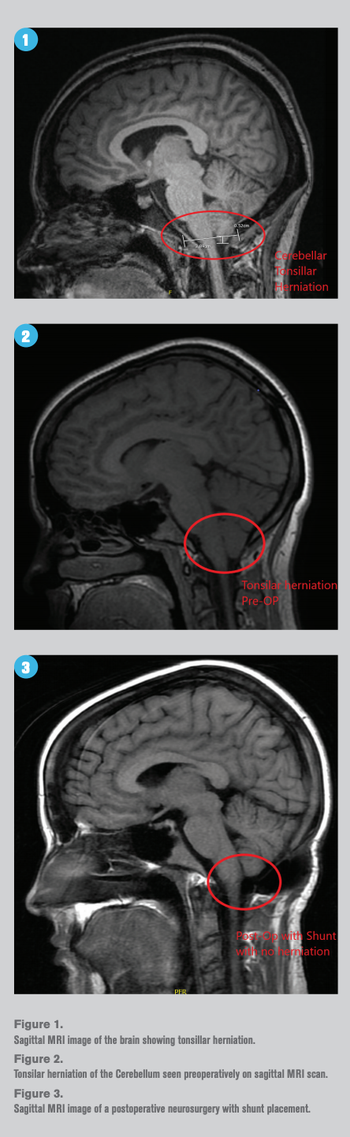

Review Chiari-related diseases and associated ocular symptomsBy James F. Hill III, OD, FAAOSeptember 17th 2020There is a role for optometrists in diagnosis and treatment of these conditions